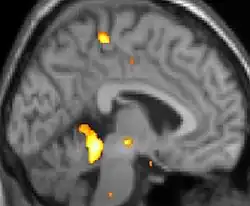

Positron emission tomography (PET) shows brain areas being activated during pain.

Positron emission tomography (PET) scans indicate the brain areas which are activated during attack only, compared to pain free periods. These pictures show brain areas that are active during pain in yellow/orange color (called "pain matrix"). The area in the center (in all three views) is activated only during cluster headaches. The bottom row voxel-based morphometry shows structural brain differences between individuals with and without CH; only a portion of the hypothalamus is different.[36]